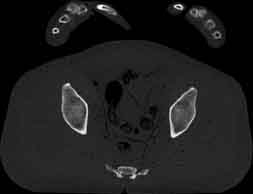

Visible Human male: Sectio transversalis 1845

CT

NMR

Pd                          / T2 \                         T1